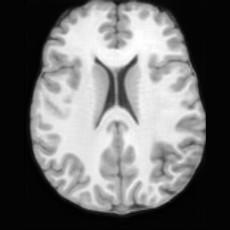

(a)PathologicalInput ImageSynthSR [18]Brain-ID [28]UNA [30]USBHealthyGround TruthRefer to captionRefer to captionRefer to captionRefer to captionRefer to captionRefer to captionRefer to captionRefer to captionRefer to captionRefer to captionRefer to captionRefer to captionRefer to captionRefer to captionRefer to captionRefer to captionRefer to captionRefer to captionRefer to captionRefer to captionRefer to captionRefer to captionRefer to captionRefer to caption(b)HealthyInput ImageConditionalLesion MaskUNA [30]USBRefer to captionRefer to captionRefer to captionRefer to captionRefer to captionRefer to captionRefer to captionRefer to captionRefer to captionRefer to captionRefer to captionRefer to captionRefer to captionRefer to captionRefer to captionRefer to caption

Figure 5: Comparison of bidirectional brain editing. (a) pathology-to-healthy, the circles and arrows highlight lesion regions and unsuccessful reconstructions; (b) healthy-to-pathology. Note that SynthSR and Brain-ID cannot perform healthy-to-pathology editing.

Pathology-to-Healthy Editing. Fig. 5 (a) presents comparison results on four input brain images with lesions of varying sizes, shapes, and densities. All competing models, although specialized for healthy brain image synthesis, struggle to reconstruct pathological regions, especially near lesion boundaries. In contrast, USB accurately reconstructs the corresponding healthy brain, even in challenging cases with large, high-density lesions where normal brain structures are almost completely obscured (last row). Tab. 2 provides a quantitative comparison for pathology-to-healthy editing, where USB achieves the best performance across all three datasets, demonstrating the effectiveness of its unified framework in reconstructing healthy brains from pathological inputs. Additional results are in Suppl. B.